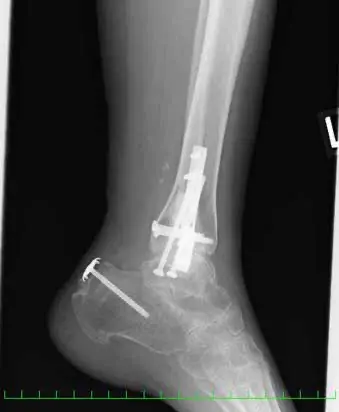

(図5)術後X線像

脛骨内果はcancellus screw2本、腓骨外果は1/3円プレート、脛骨天蓋部は骨欠損部にオスフェリオンを充填し、cancellus screw2本にて固定している。踵骨裂離骨片はスパイクワッシャー付cancellus screwにて固定し、Leeds-Keio人工靭帯にて補強している。